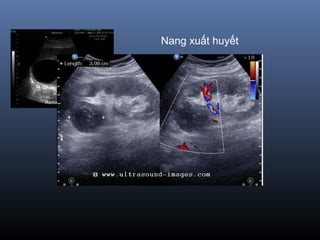

 Nang xu t huy t : đauấ ế

 Nang xu t huy t : d ch tăng đ m đ (60 UH)ấ ế ị ậ ộ

Siêu âm

 T n th ng tròn , echo tr ng đ ng nh t, vổ ươ ố ồ ấ ỏ

r t m ngấ ỏ

 V trí: v , c nh bê th nị ỏ ạ ậ

 Nhi m trùng, xu t huy t=> d ch bên trong sễ ấ ế ị ẽ

không còn đ ng nh t và tăng nhồ ấ ẹ

 Chuy n ác tính : vách d y, n t ++, vôi +ể ầ ố

 => phân lo i Bosniakạ

Nang xuất huyết